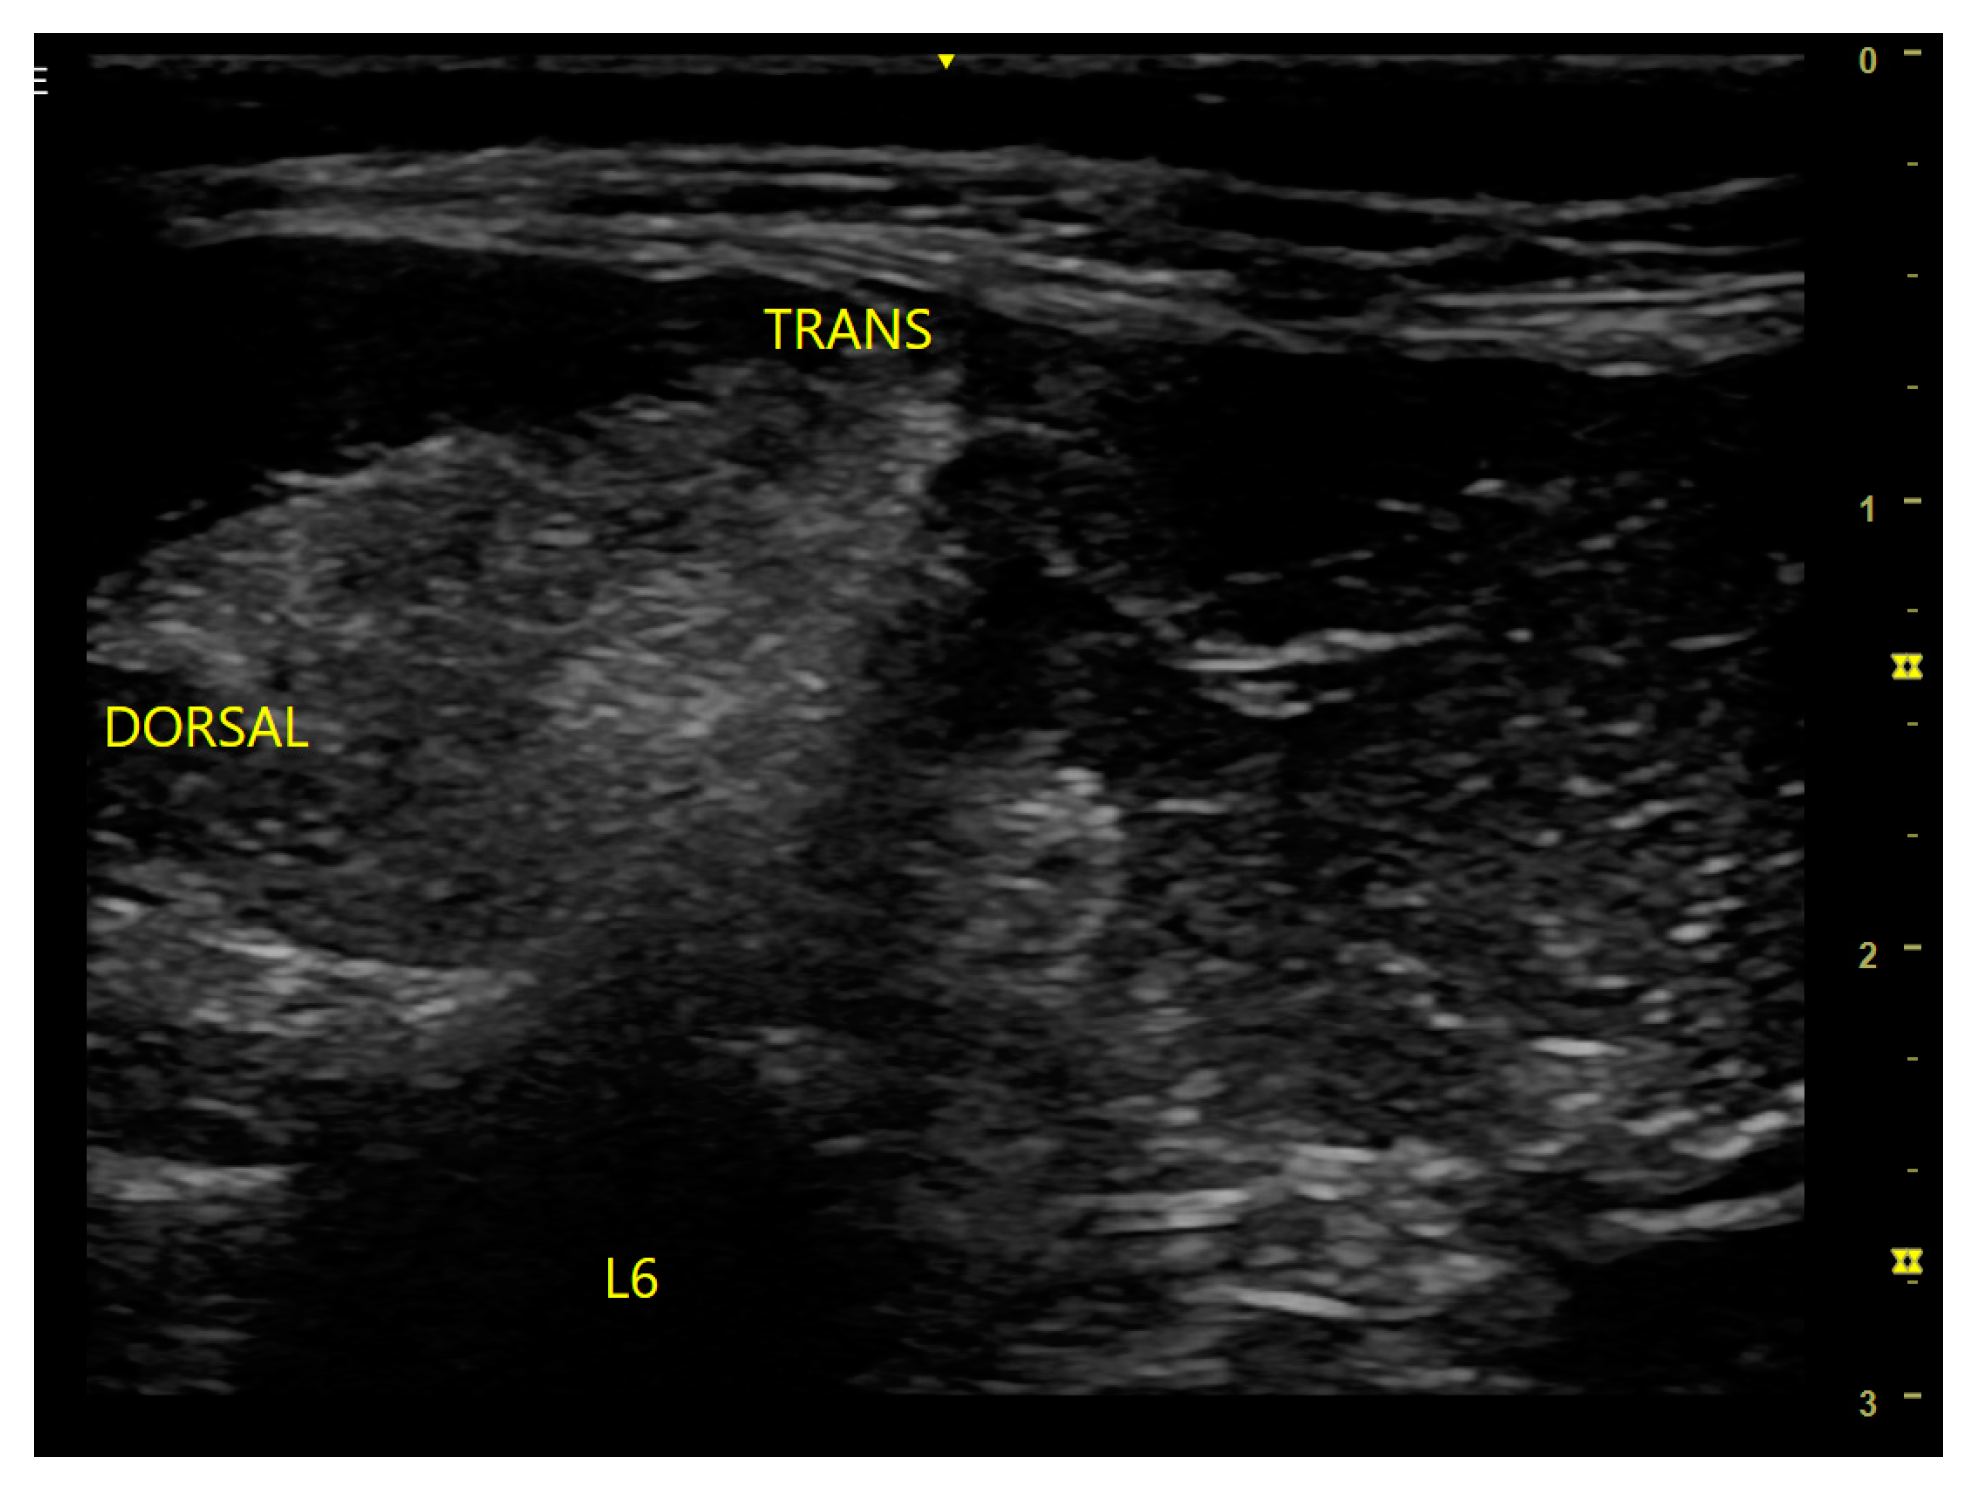

7.2. Brachial Plexus Block

- Portela, D.A.; Otero, P.E.; Sclocco, M.; Romano, M.; Briganti, A.; Breghi, G. Anatomical and radiological study of the thoracic paravertebral space in dogs: Iohexol distribution pattern and use of the nerve stimulator. Vet. Anaesth. Analg. 2012, 39, 398–408. [Google Scholar] [CrossRef] [PubMed]